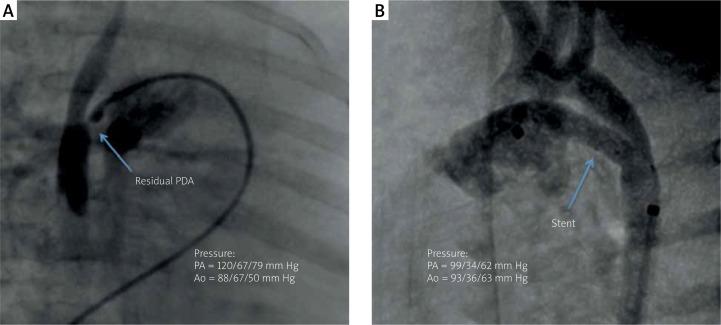

PDA stenting in 6-month-old infant with suprasystemic pulmonary hypertension as a treatment option for hypertensive crisis.